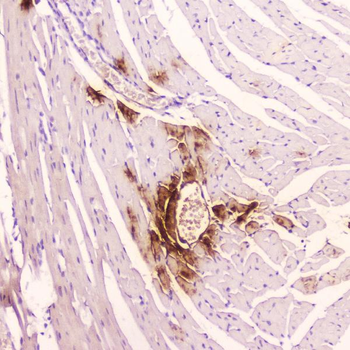

−| Tested Applications | ELISA, IHC, WB |

| Dilution range | WB: 1: 500-1: 2000, IHC-P: 1: 50-1: 200 |

NPPA Antibody (orb682926)